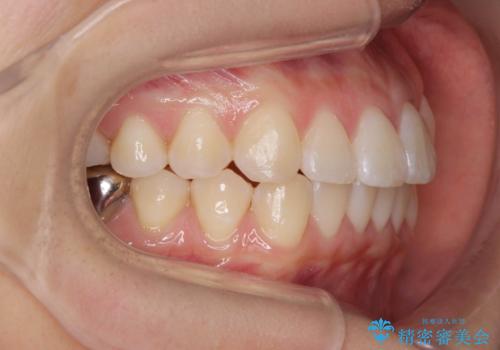

正中のズレ、引っ込んだ前歯の矯正

- 噛んだ時の前歯正中のズレ、引っ込んでいる前歯を治したい。と矯正治療を希望され来院されました。

左上2の前歯はスペースが足りないため、後方に引っ込んでしまっている状態です。

マウスピース矯正システムインビザラインで歯の後方移動、咬合関係の修正を行ったのち、引っ込んでいる左上2をワイヤーを用いて短時間で引き出す治療計画としました。

部分ワイヤー矯正を行なったことで約3ヶ月という短期間で前歯を綺麗に並べることができました。